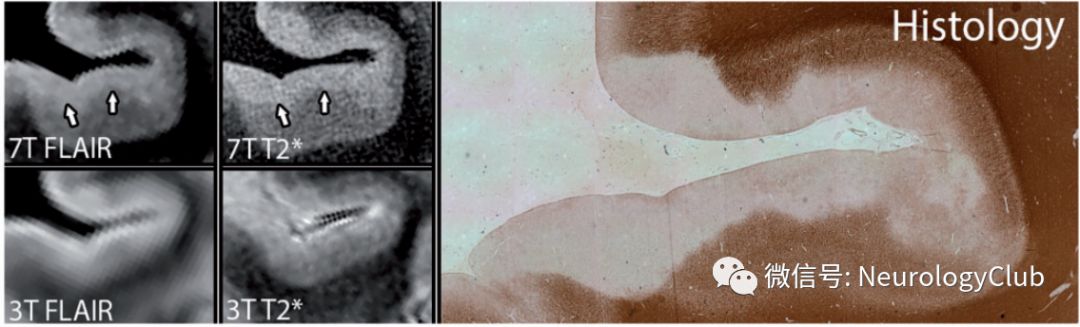

皮质病灶分4型,I型(皮质-白质混合型),病灶累及皮质深层及其相邻白质 ;II型(皮质内型),以血管为中心的小的脱髓鞘病变,局限于皮质内 ;III型,病灶从软脑膜表面延伸入皮质;IV型,病灶累及全皮质层而未累及皮质下白质;III型和IV病变简称为软膜下型病变,可以是局限的,也可能累及多个相邻的脑回,甚至可以累及所有皮质区域,但未累及皮质下的白质,称为“广泛软脑膜下脱髓鞘”。

在多发性硬化中,软脑膜下脱髓鞘和脑膜炎症以及鞘内促炎因子的改变有关。病理研究提示这类皮层病灶对多发性硬化的诊断具有高度特异性,且累及范围广。

但是,软脑膜下脱髓鞘在一般场强MRI下较难识别。用T2*或MP2RAGE序列的超高场强MRI可有助于识别,目前,软脑膜下脱髓鞘这一征象尚不能用于日常临床实践,识别这类病灶的标准化流程有待进一步改进。

图7:MRI上的4型皮质病灶

图8:7T上可见但3T上未见的III型病变